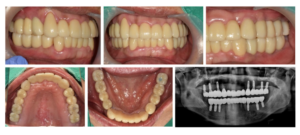

모든 치료가 마무리된

구강 내 사진과

파노라마 사진인데요.

환자분께서는

그동안 앞니로 식사하시면서

불편감이 많으셨는데

치료 후 양측 저작이 편안하게 잘 되고

전보다 심미적으로 변한 모습에

만족해하셨습니다.

전 > 후